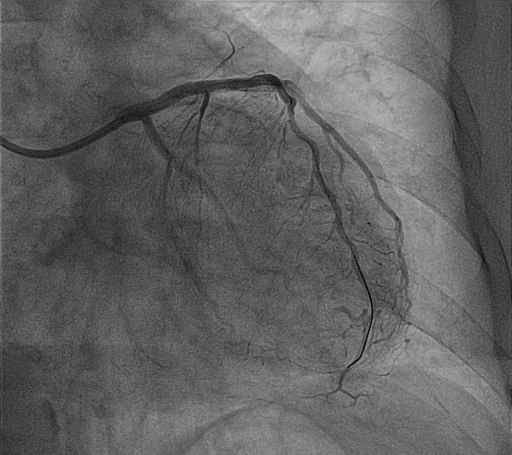

植入支架

经过充分的冲击波球囊预处理后,因钙化环得到松解,血管顺应性提升,病变处顺利植入支架2枚。术后造影提示支架贴壁良好,扩张满意,无残余狭窄。

成功置入支架,支架贴壁良好,扩张满意,无残余狭窄